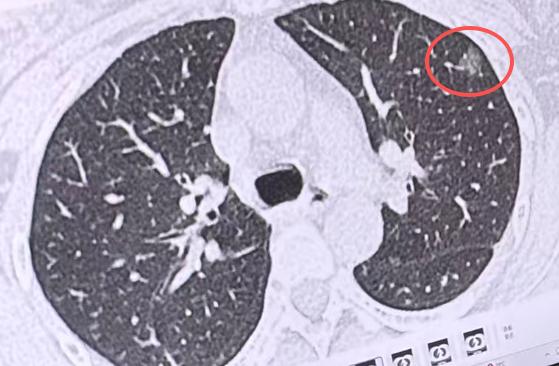

吸烟、环境污染、病毒,哪一个和肺癌更相关,大部分人的认知误区肺癌是全国第一大癌

肺癌